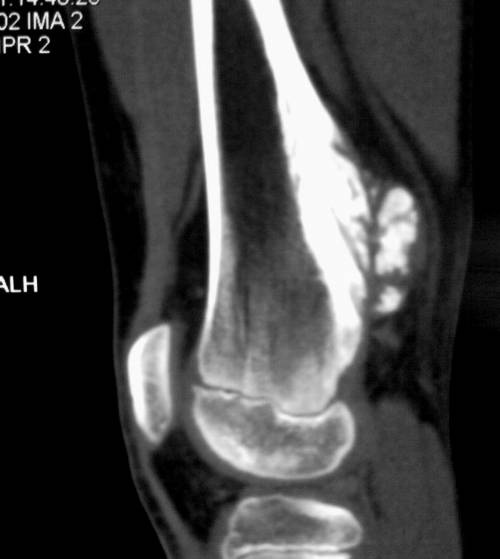

- Компьютерная томография

- участки некроза внутри опухоли

- живые опухолевые клетки сосредоточены вокруг сосудов

- поражение мягких тканей вокруг опухоли, превосходящее по размеру саму опухоль

- размягчение связок и сухожилий вблизи опухоли

- очаги поражения костного мозга